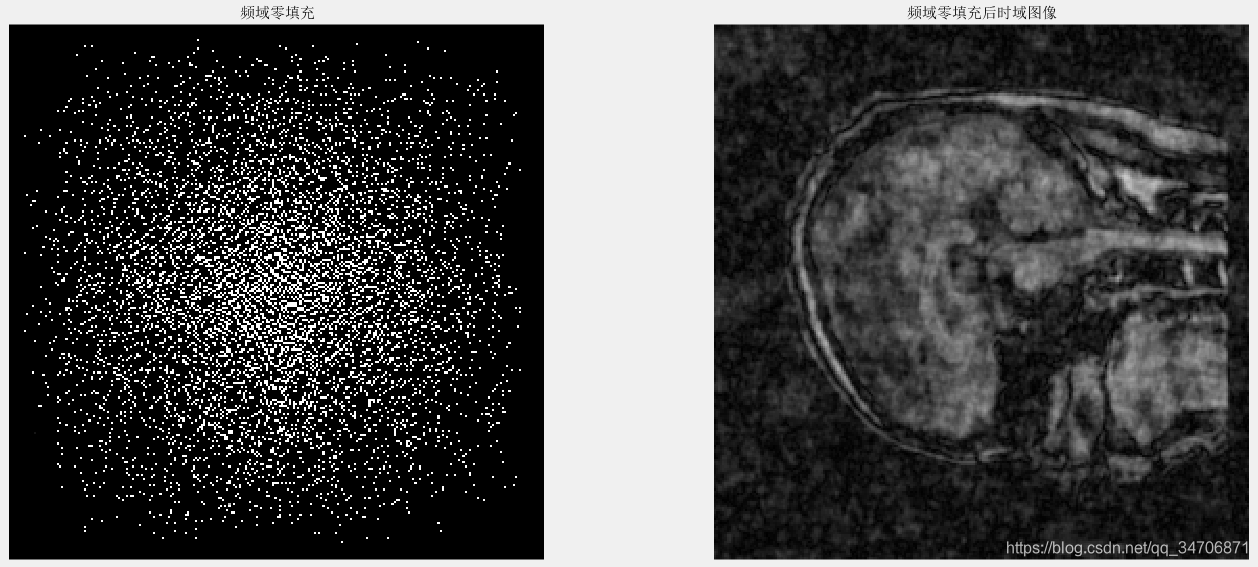

我们主要关注的是第三个方法,欠采样——>再重建。由欠采样图像去重建一幅全采样图像(真实图像),显然是一个NP难的问题(很多全采样图像能对应同一幅欠采样图像)。由于欠采样违反了奈奎斯特采样定理,直接进行频域零填充的时域图像上会发生混叠伪影,如图1、2、3所示。